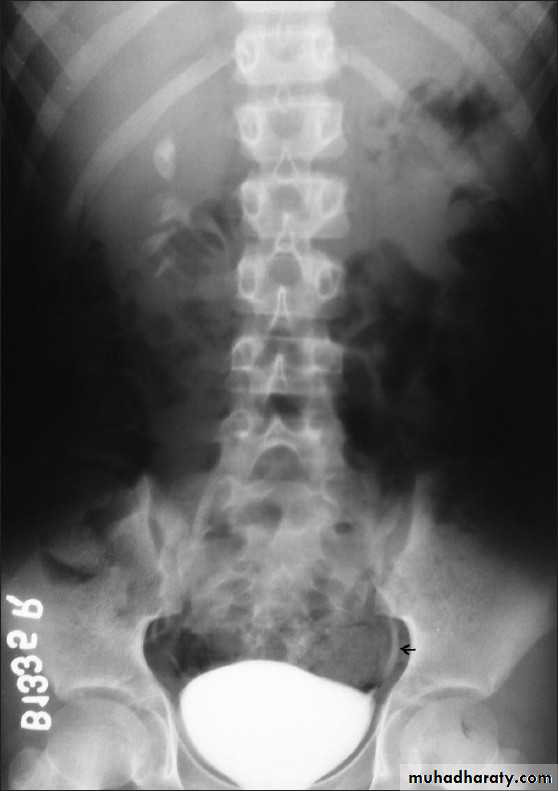

Retrocaval ureter :

The middle third of right ureter curve medially behind the IVC , then laterally to regain it’s normal position , this lead to obstruction of upper third of ureter.Ureterocele :